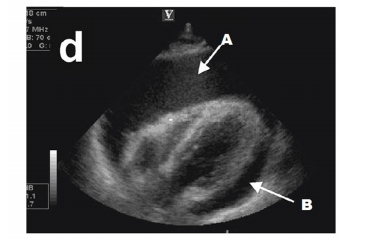

A figura a seguir representa qual provável etiologia para justificar uma PCR?